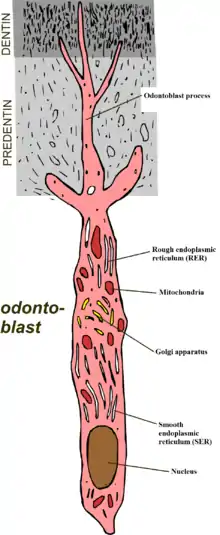

The odontoblastic transduction theory was suggested by Rapp et al. and puts forward the idea that odontoblasts act as receptor cells, and conduct impulses via synaptic junctions to the end of the nerves and therefore cause the feeling of pain. However, there is not much evidence to support this theory.

The neural theory proposes that thermal or mechanical stimuli can directly influence nerve endings within the dentinal tubules via direct communication with the nerve endings of the pulp.